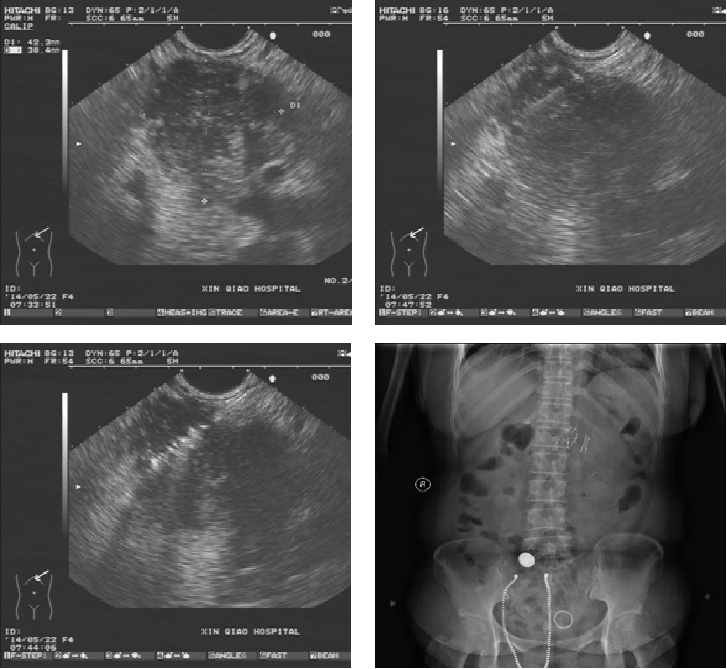

超声内镜引导下I125置入治疗胰腺癌